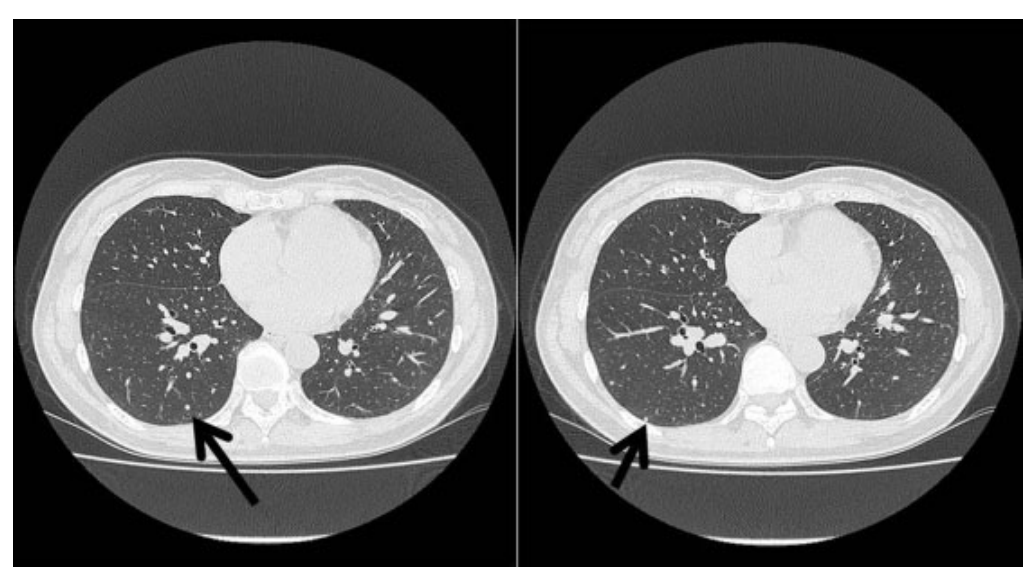

图1. 胸部CT显示多发界限清楚的结节,箭头表示活检切除的结节。

图2. 箭头表示术前胸部CT显示双肺囊肿。

一名47岁的女性因与月经周期相关的复发性气胸入院,怀疑为月经性气胸,术前胸部CT显示双肺存在多个肺结节和囊肿(见图1-2)。患者在12年前接受了剔除性子宫肌瘤切除术。18-氟脱氧葡萄糖正电子发射断层扫描结果显示,全身未见异常摄取。此外,肿瘤标志物检测显示癌胚抗原、鳞状细胞癌相关抗原和细胞角蛋白19片段均在正常范围内。基于这些发现,怀疑患者可能患有良性转移性平滑肌瘤(BML)、淋巴血管平滑肌瘤(LAM)或其他转移性肿瘤。因此,决定进行了胸腔镜活检,以便进一步的诊断和治疗。